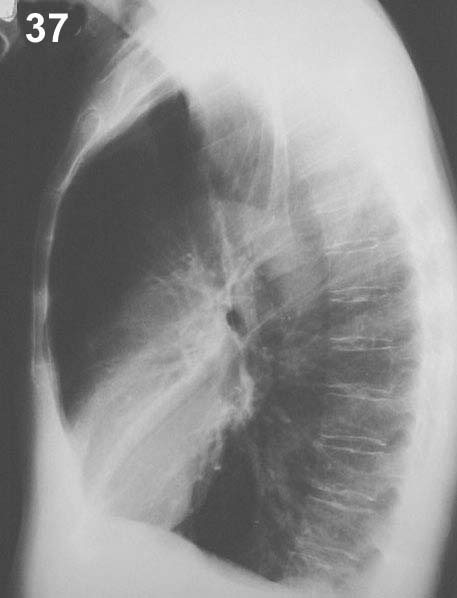

Placa 37